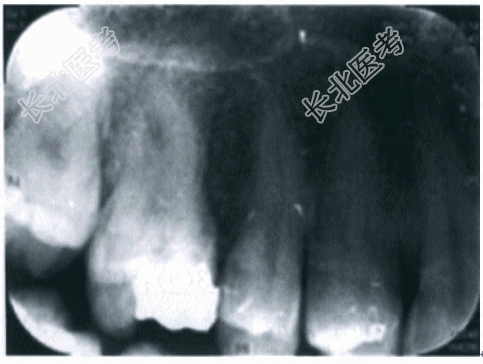

面可见大块牙色充填体,探诊充填体边缘密合,牙齿无探痛,垂直叩诊(+++),侧向叩诊(+),扪诊根尖部(+),无波动感,松动Ⅰ度,冷诊无反应,电活力测试无反应;牙龈略红肿,触诊不痛;根尖部颊黏膜红肿;余牙检查无特殊情况。5.辅助检查 X线片检查示:16冠部充填物影像,牙周膜间隙增宽,髓室及近中颊根管影像不清,根尖未见明显异常(见图10-1)。